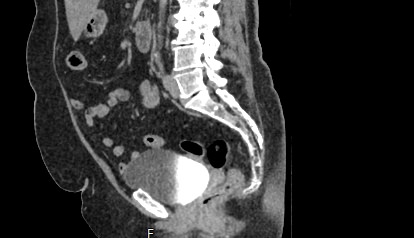

Мультиспиральная компьютерная томография органов малого таза включает в себя исследование женских половых органов (матка, яичники) или мужских половых органов (предстательная железа, семенные пузырьки, семявыносящие протоки), а также мочевого пузыря с мочеточниками на видимом протяжении, прямой кишки, тазовой брюшины, лимфатических узлов, мягких тканей малого таза.

Нативная компьютерная томография таза проводится без использования контраста. Однако при подозрении на патологические изменения со стороны органов мужской или женской половой сферы, мочевыделительной системы, прямой кишки или окружающих мягких тканей, обязательным является внутривенное введение йодсодержащего контрастного препарата. Контрастный препарат в большей степени накапливается в патологически измененных участках и обеспечивает их яркую визуализацию на фоне здоровых тканей. Это используется для диагностики онкологических заболеваний на ранних стадиях, что имеет решающее значение для жизни и здоровья пациента.

В результате получаются снимки тончайших срезов исследуемой зоны с высокой степенью детализации, на основе которых производится объемная реконструкция органов малого таза, что позволяет проводить точную диагностику. Трехмерные модели дают информацию о пространственном расположении органов и патологических образований, что важно, например, при планировании оперативных вмешательств и в дальнейшем при оценке эффективности операции и проведенного лечения.

Мультиспиральная компьютерная томография используется для диагностики аномалий развития, травматических повреждений, воспалительных заболеваний и опухолевых процессов органов малого таза. Преимуществами данного исследования является высокая скорость сканирования и доступная цена. Однако в ряде случаев может быть более предпочтительно выполнение магнитно-резонансной томографии, которая обладает высокой чувствительностью и информативностью для обследования органов и мягких тканей малого таза. В клинике «Доступная медицина» МРТ малого таза можно пройти на нашем современном оборудовании экспертного уровня.